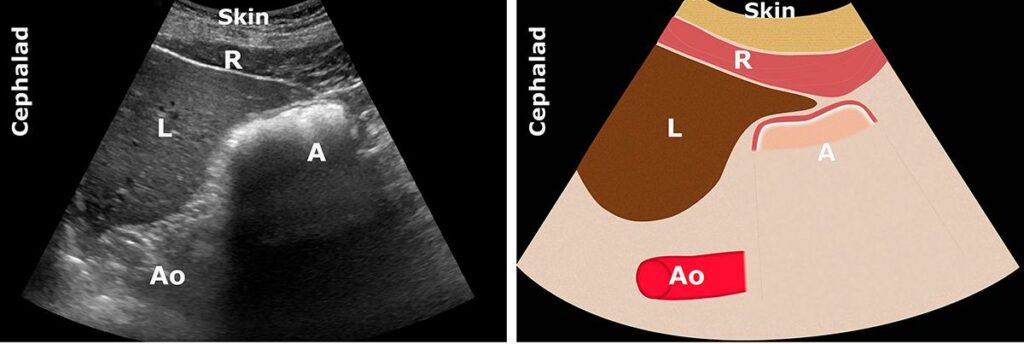

BOŞ MİDE

A: Antrum; Ao: Aort; C: Kolon; L: Karaciğer; P: Pankreas; SI: İnce bağırsak; Sma: Süperior

mezenterik arter

Antrumun hem supin hem de RLD’de kayda değer bir içeriği yoktur (Grade 0 antrum). Düz ve kollabe olmuş veya yuvarlak oval bir şekle sahip görünür (“bull’s eye” veya “target” paterni).